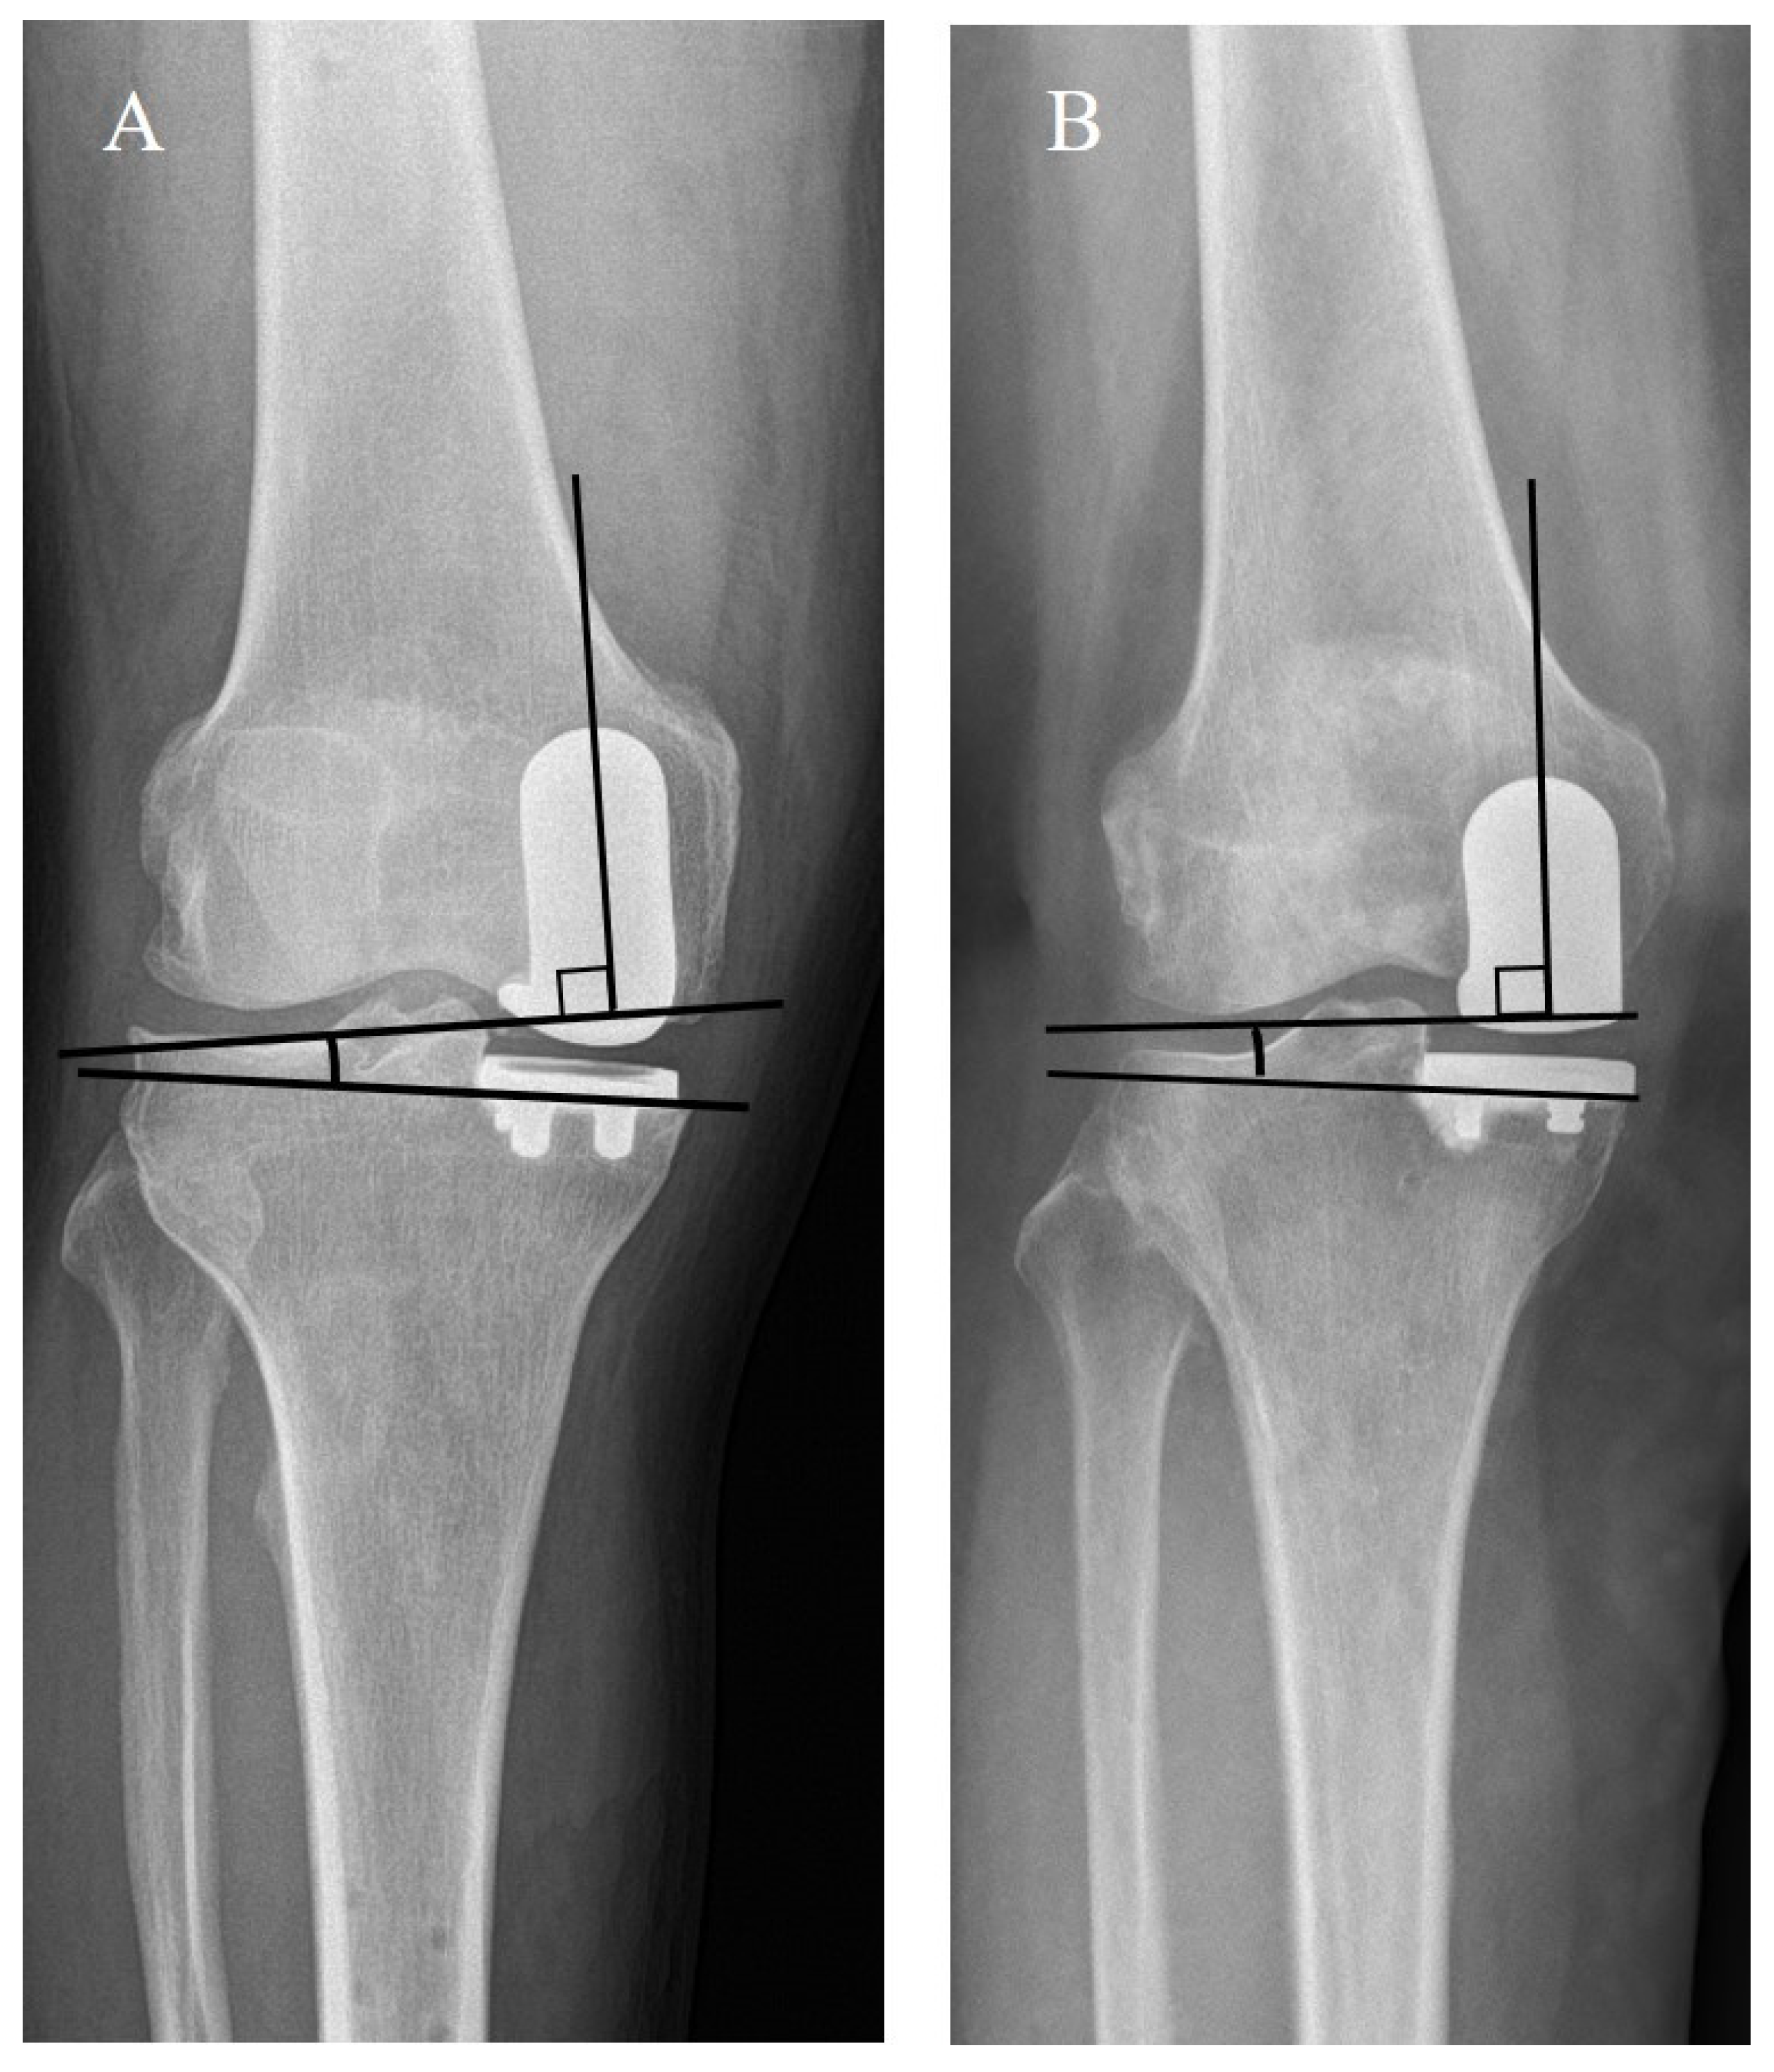

4. Clinical and Radiological Assessment

| Coronal femoral component angle (α) (°) | 2.4 ± 4.9 | −1.1 ± 3.2 | <0.001 |

| Coronal tibial component angle (β) (°) | −1.0 ± 4.3 | −3.0 ± 2.4 | 0.001 |

| Coronal FT component congruence angle (°) | 3.4 ± 4.5 | 1.9 ± 2.6 | 0.028 |